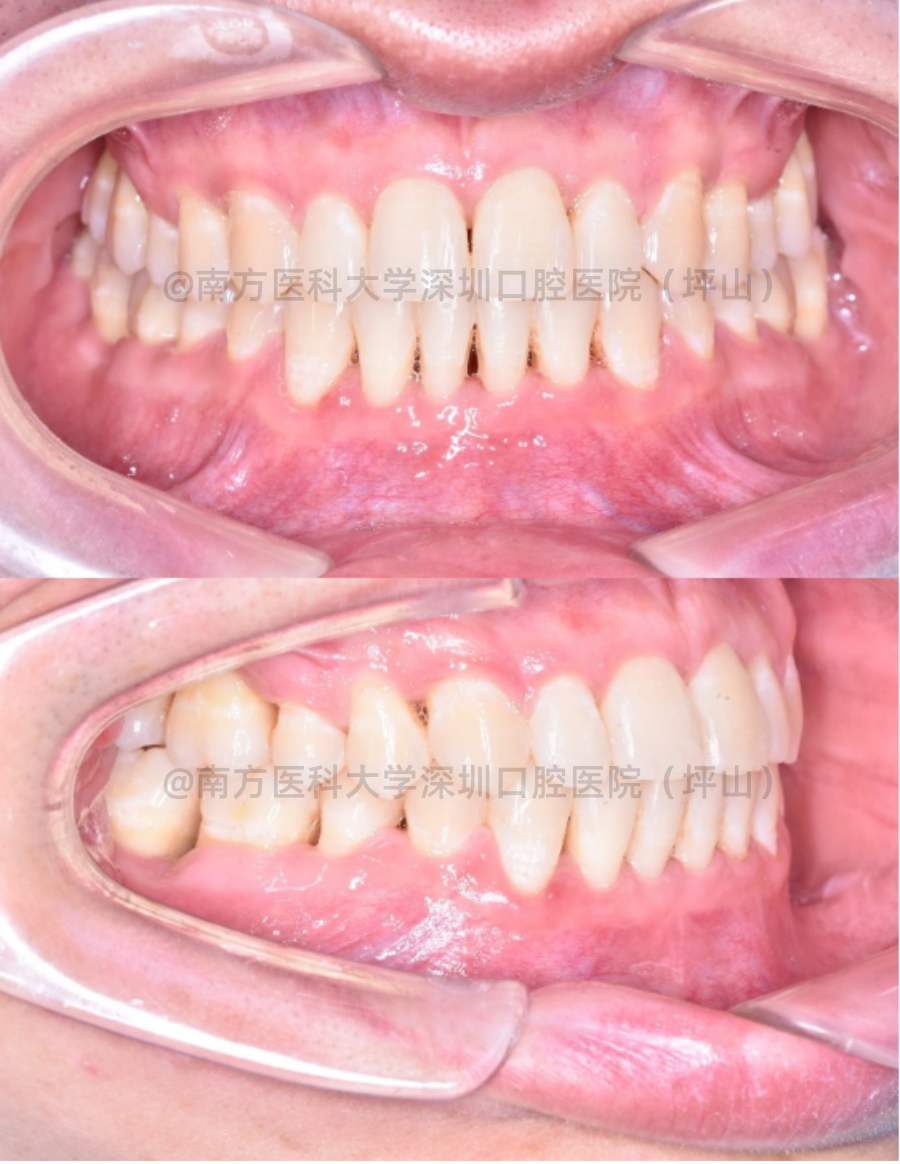

矫治过程回顾

矫治前

矫治后

整个矫正时间历时1年4个月,通过医生及患者的积极配合,最终达到了患者满意的效果。